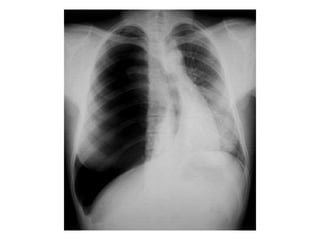

• Chest X-ray PA view showing the sharply

defined edge of the deflated lung with

complete translucency (no lung markings, no

vascular markings) between this and the chest

wall in the Rt side with shifting of

mediastinum to left.

• Suggestive of Rt Tension Pneumothorax

Pneumothorax